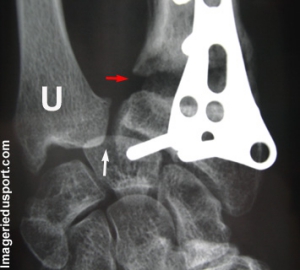

A - Radiographie du poignet droit de face : Solution de continuité large au niveau du foyer fracturaire métaphysaire distal du radius. noter la variance ulnaire positive.

Pseudarthrose large du Radius.